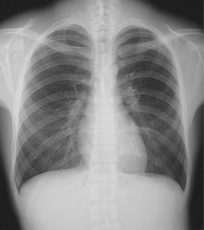

¾Àþ¡ÊÊü¼ÍÀþ¡Ë¤òÍøÍѤ·¡¢¶»Éô¡¢Ê¢Éô¡¢¹ü¤Ê¤É¤Î¾õÂÖ¤ò´Ñ»¡¤·¤Þ¤¹¡£Åö±¡¤Ç¤Ï¡¢¾¯¤Ê¤¤XÀþÎ̤ÇÁ¯ÌÀ¤Ê²èÁü¤¬»£±Æ¤Ç¤¤ëÁõÃÖ¤òƳÆþ¤·¤Æ¤¤¤Þ¤¹¡£³Ø²ñ¤«¤é¤â¡Ö°åÎÅÈï¤Ð¤¯Ä㸺»ÜÀߡפȤ·¤ÆÇ§Äê¤ò¼èÆÀ¤·¡¢°Â¿´¤·¤Æ¸¡ºº¤ò¼õ¤±¤Æ¤¤¤¿¤À¤±¤Þ¤¹¡£»õÁ´ÂΤÎÍͻҤò´Ñ»¡¤¹¤ë¥Ñ¥ó¥È¥â»£±Æ¤â¹Ô¤Ã¤Æ¤¤¤Þ¤¹¡£